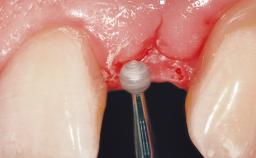

A 39-year-old male patient presented with a chief complaint of discomfort and gingival discoloration around his maxillary left central incisor. He was in good general health and was a non-smoker. His past dental history was significant because of the traumatic fracture of tooth 21 in a sporting accident at age 13. Initial dental treatment included endodontic therapy and a full-coverage restoration. The patient became symptomatic 5 years later, when structural failure of the tooth resulted in the dislodgment of the crown. Endodontic retreatment, apical surgery, and post-and-core restoration were performed.

Placement Protocol Early or late implant placement

Bone Volume Deficient horizontally, requiring prior grafting